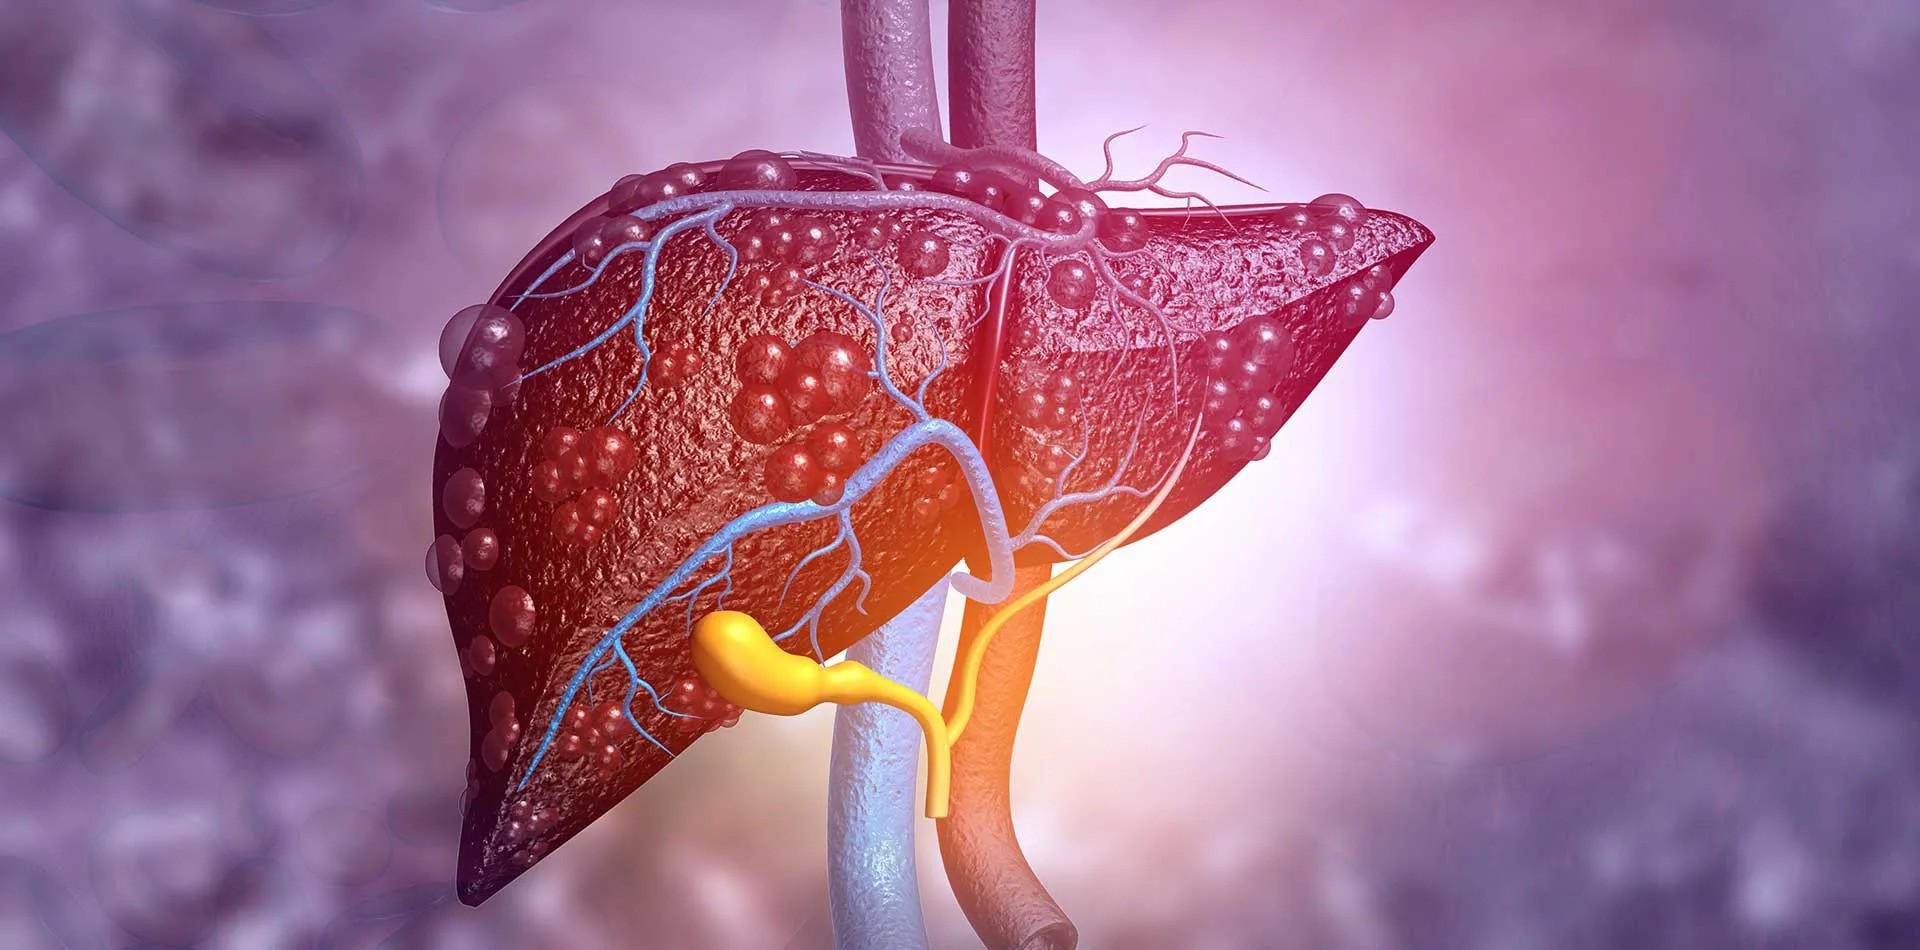

همانژیوم کبد : همانژیوم کبدی (he-man-jee-o-muh) یک توده غیرسرطانی (خوش خیم) در کبد است که از درهم پیچیده ای از رگ های خونی تشکیل شده است. همچنین به عنوان همانژیوم کبدی یا همانژیوم غاری شناخته می شود، این توده های کبدی شایع هستند و تخمین زده می شود که در 20٪ از جمعیت رخ دهند.

همانژیوم کبدی یک توده غیرسرطانی (خوش خیم) در کبد است. همانژیوم کبد از درهم تنیده ای از رگ های خونی تشکیل شده است. اکثر موارد همانژیوم کبدی در طی یک مطالعه تصویربرداری انجام شده برای برخی شرایط دیگر کشف می شوند. افرادی که همانژیوم کبدی دارند به ندرت علائم و نشانه هایی را تجربه می کنند و معمولاً نیازی به درمان ندارند. ممکن است دانستن توده در کبدتان ناراحت کننده باشد، حتی اگر توده ای خوش خیم باشد. با این حال، هیچ مدرکی مبنی بر اینکه همانژیوم کبدی درمان نشده می تواند منجر به سرطان کبد شود، وجود ندارد.

همانژیوم کبد : مشخص نیست که چه چیزی باعث ایجاد همانژیوم کبدی می شود. پزشکان معتقدند همانژیوم کبد در بدو تولد وجود دارد (مادرزادی). همانژیوم کبدی معمولاً به صورت مجموعه ای غیرطبیعی از رگ های خونی رخ می دهد که عرض آن کمتر از حدود 1.5 اینچ (حدود 4 سانتی متر) است. گاهی اوقات همانژیوم کبدی می تواند بزرگتر باشد یا به صورت چند قلو رخ دهد. همانژیوم بزرگ ممکن است در کودکان خردسال رخ دهد، اما این نادر است.

در بیشتر افراد، همانژیوم کبد هرگز رشد نمی کند و هیچ علامت و نشانه ای ایجاد نمی کند. اما در تعداد کمی از افراد، همانژیوم کبدی رشد می کند تا علائم ایجاد کند و نیاز به درمان دارد. معلوم نیست چرا این اتفاق می افتد.